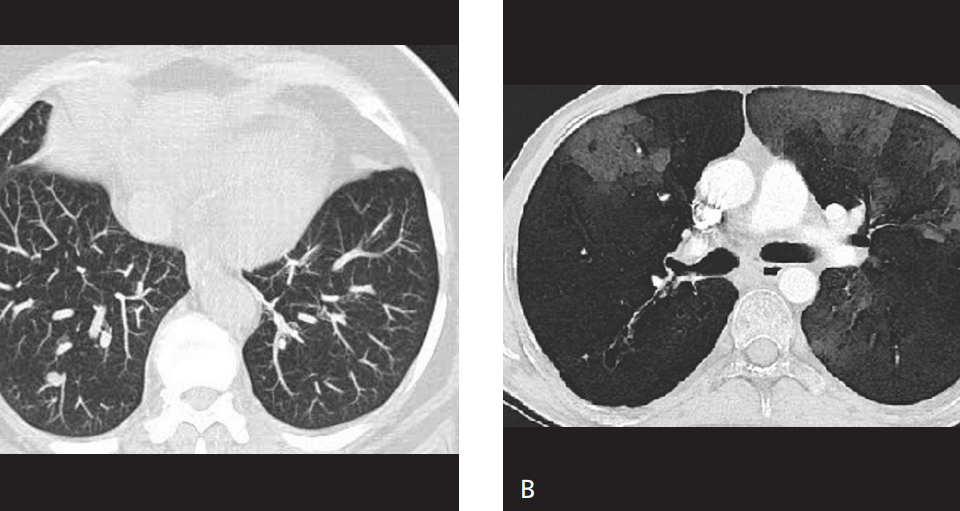

Her açıdan en düşük dansite değerine sahip voksellerin birleştirilerek iki boyutlu görüntüye aktarılması ile oluşturulur. Sarus PACS MinIP aracı ile sadece hava dansitesine eşit ya da […]